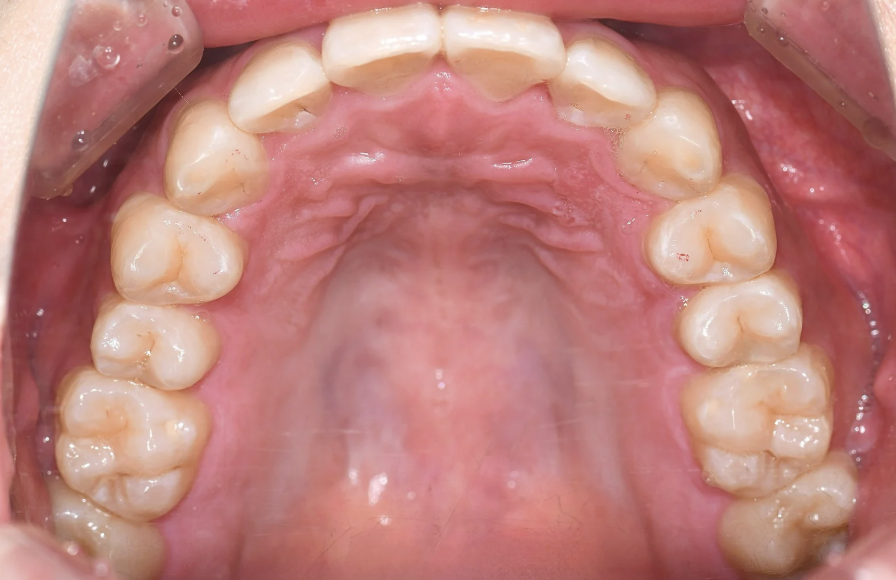

永久歯に大きさに対し、歯を並べるスペース(顎)が小さく、

上下ともに狭窄歯列、下顎前歯には叢生(歯のガタつき)、上顎前歯の突出感が認められました。

また、やや上の前歯が下の前歯に覆い被さり、噛み合わせが深い(ディープバイト)傾向もあり、奥歯への負担が強くかかる噛み合わせでした。